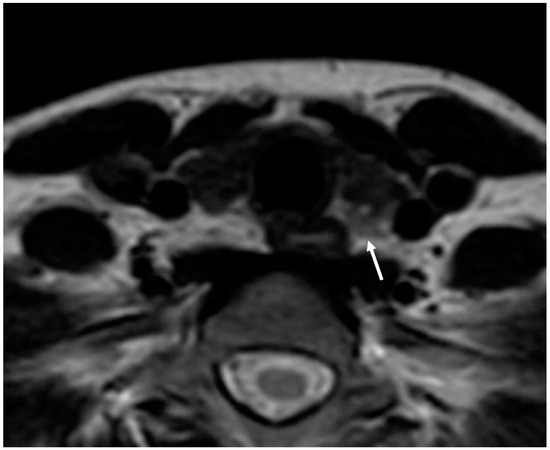

MRI